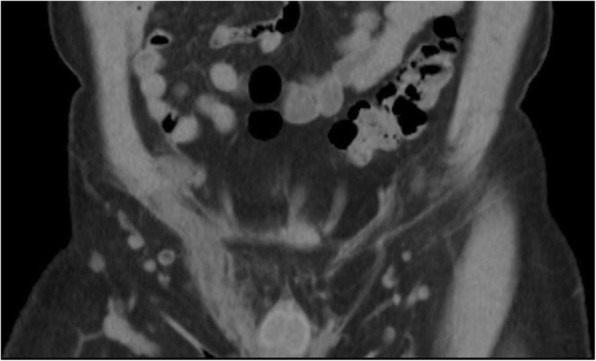

Fig. 1.

Non-enhanced coronal CT image revealed diffuse edematous change of right spermatic cord (white arrow)